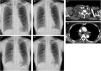

CXR images (A, B, E, and F), contrast-enhanced chest computed tomography images (C and D). (A) Before the initiation of CPAP therapy. (B–D) Two days after the initiation of CPAP therapy. (E) The day after the discontinuation of CPAP therapy. (F) One week after the discontinuation of CPAP therapy. CPAP=continuous positive airway pressure; CXR=chest X-ray.

A 78-year-old female non-smoker with a history of hyperlipidemia complained of daytime sleepiness, and her family pointed out her snoring. The patient did not complain of pain in the neck, chest, shoulders, and upper limbs and dysesthesia such as paresthesia, hypoesthesia, or weakness. Her body mass index was 19.2kg/m2. Chest X-ray (CXR) revealed no abnormal findings (Fig. 1A). Polysomnography using Alice 6® (Philips Respironics; Murrysville, Pennsylvania, USA) was performed. Diagnostic polysomnography revealed that the apnea–hypopnea index (AHI) was 83.0events/h, comprising 57.3events/h of obstructive apnea, 1.3events/h of mixed apnea, 0.3events/h of central apnea, and 24.1events/h of hypopnea. Thus, the patient was diagnosed with severe obstructive sleep apnea. Continuous positive airway pressure (CPAP) therapy was introduced using an auto-titrating device (DreamStation®; Philips Respironics), which was set to auto mode (pressure setting: 4–6cmH2O). Polysomnography under CPAP therapy revealed that AHI was 8.3events/h. Diagnostic polysomnography and polysomnography under CPAP therapy showed no evidence of ventricular arrhythmia, such as premature ventricular contraction and non-sustained ventricular tachycardia. The patient's physical condition did not change after one day of the initiation of CPAP therapy. However, two days after the initiation of CPAP therapy, she complained of malaise and right-sided cervical swelling a few hours after switching the CPAP device off. On the other hand, she did not complain of headache. Physical examination revealed swelling in the right supraclavicular fossa. The D-dimer level was 1.4μg/mL. CXR revealed the enlargement of the superior mediastinum and the deviation of the trachea to the left (Fig. 1B). Although contrast-enhanced chest computed tomography revealed no evidence of thrombus and lymph node enlargement, edematous change of the right-sided subcutaneous structure and the mediastinum and right pleural effusion were detected (Fig. 1C and D). Thus, we discontinued CPAP therapy without any treatments. The next day, the follow-up CXR revealed improvement in the enlargement of the superior mediastinum and tracheal deviation; however, this CXR also revealed a slightly increased right pleural effusion (Fig. 1E). Physical examination revealed improvement of swelling in the right supraclavicular fossa. One week later, the follow-up CXR revealed improvement in the patient's right pleural effusion (Fig. 1F).